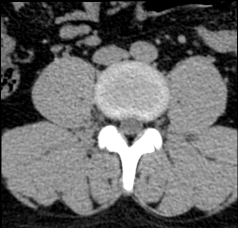

Chẩn đoán hình ảnh mô mềm tiên tiến cho vùng bụng.

Tăng cường độ tương phản I-ốt.

Hỗ trợ đánh giá an toàn cho bệnh nhân.

Đảm bảo hình ảnh chất lượng cao.